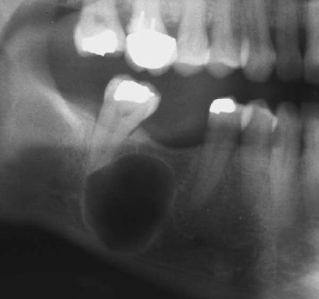

how would you describe this radiographic lesion?

a multilocular radiolucent lesion